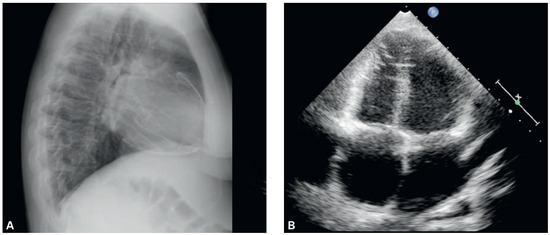

Chest X-ray (Figure 1, panel A) showed pericardial calcification, confirmed by computed tomography of the thorax, and also revealed bilateral mediastinal, hilar and supraclavicular lymphadenopathy. Transthoracic echocardiography (panel B) demonstrated typical septal bouncing suggestive of constrictive pericarditis. Doppler echocardiography of the mitral inflow demonstrated an E/A ratio >3 and short E wave decelaration times (<150 ms). As shown in panel C, E wave velocity decreased from 80 cm/s to 48 cm/s during inspiration and we observed flow reversal in the hepatic vein during expiration. Additionally, although not typical for constrictive pericarditis, we observed reduction of right ventricular function. The typical constrictive physiology with dip-and-plateau pattern (“square root sign”) was confirmed on right-left heart catheterisation. In fact, diastolic pressure equalisation (20 mm Hg) in all cardiac chambers was observed. As a result of right heart failure, liver dysfunction (international normalised ratio 3.2) and hypertensive gastro-pathy on gastroscopy were identified. Owing to the patient’s country of origin, young age and aetiological probabilities based on epidemiological findings [1,2], we have postulated tuberculous pericarditis as the cause of the pericardial calcification and constrictive heart failure. Therapeutic pericardiectomy was performed without complications (panel D) and the histological examination of the pericardial tissue indicated pericardium calcification (panels E and F) and inflammation with epithelioid granulomas supporting our primary assumption. As expected, a biopsy specimen for mycobacterial smear and culture was in that stage of disease negative. Antituberculosis medication was established for 8 months with initial anti-inflammatory therapy with corticosteroids [3]. The patient recovered satisfactorily after rehabilitation.

Figure 1.

Panel A: Chest X ray showing calcification of the pericardium. Panel B: Transthoracic echocardiography demonstrating constrictive diastolic physiology. Panel C: Echocardiographic result presenting the decrease of E-wave velocity during inspiration. Panel D: Intraoperative finding of pericardial calcification. Panels E and F: Histological examination of calcified pericardium, haematoxylin-eosin stain, 40×.